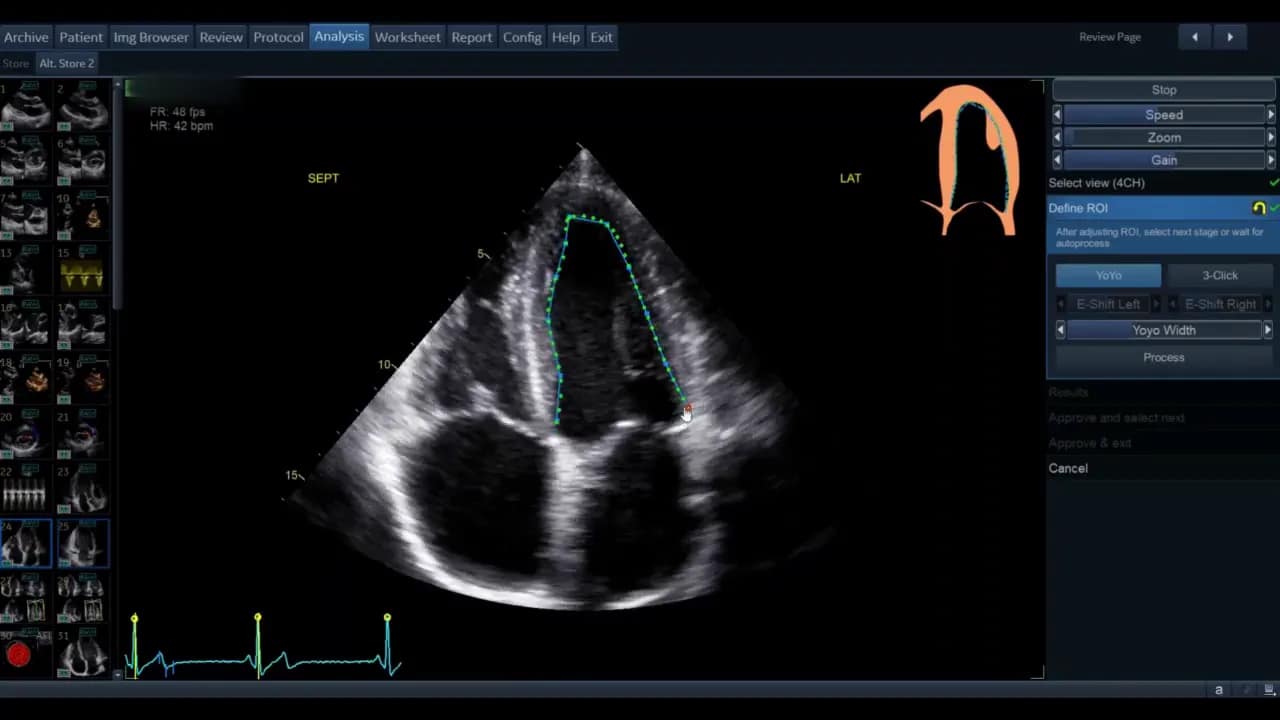

Schritt 3: Region of Interest (ROI) definieren

Sobald die Ansicht gewählt ist, gelangen Sie in die Phase der ROI‑Definition. Hier legt die Software die initiale Kontur für die automatische Wandsegmentverfolgung fest.

Die Standardkontur wird als grüne Linie (modellabhängig) angezeigt. Bewegen Sie den Cursor über diese Linie; rote Kreise erscheinen als Griffpunkte, die Sie anklicken, verschieben und loslassen können. Ziel ist eine möglichst genaue Platzierung entlang des inneren Myokardrandes ohne Papillarmuskeln und Trabekel zu ignorieren, soweit die Software dies zulässt.

- Wenn die vorgegebene Kontur passend ist, genügt das geringe Feintuning.

- Wenn die Kontur unbrauchbar erscheint, nutzen Sie die Drei‑Punkt‑Option. Dabei markieren Sie basal‑septal, basal‑lateral und den Apex manuell. Die Software interpoliert zwischen den Punkten.

Nach der manuellen Markierung können Sie die so erzeugte grüne Kontur wiederum per Griffpunkte feinjustieren. Ziel ist, dass die Kontur den endokardialen Rand im gesamten Zyklus plausibel abdeckt.

Schritt 4: Prozessierung und Erkennung von Enddyastole/Endsystole

Klicken Sie auf Process, um die automatische Verfolgung starten zu lassen. Die Software identifiziert dann den Enddiastolen‑ und Endsystolen‑Frame.